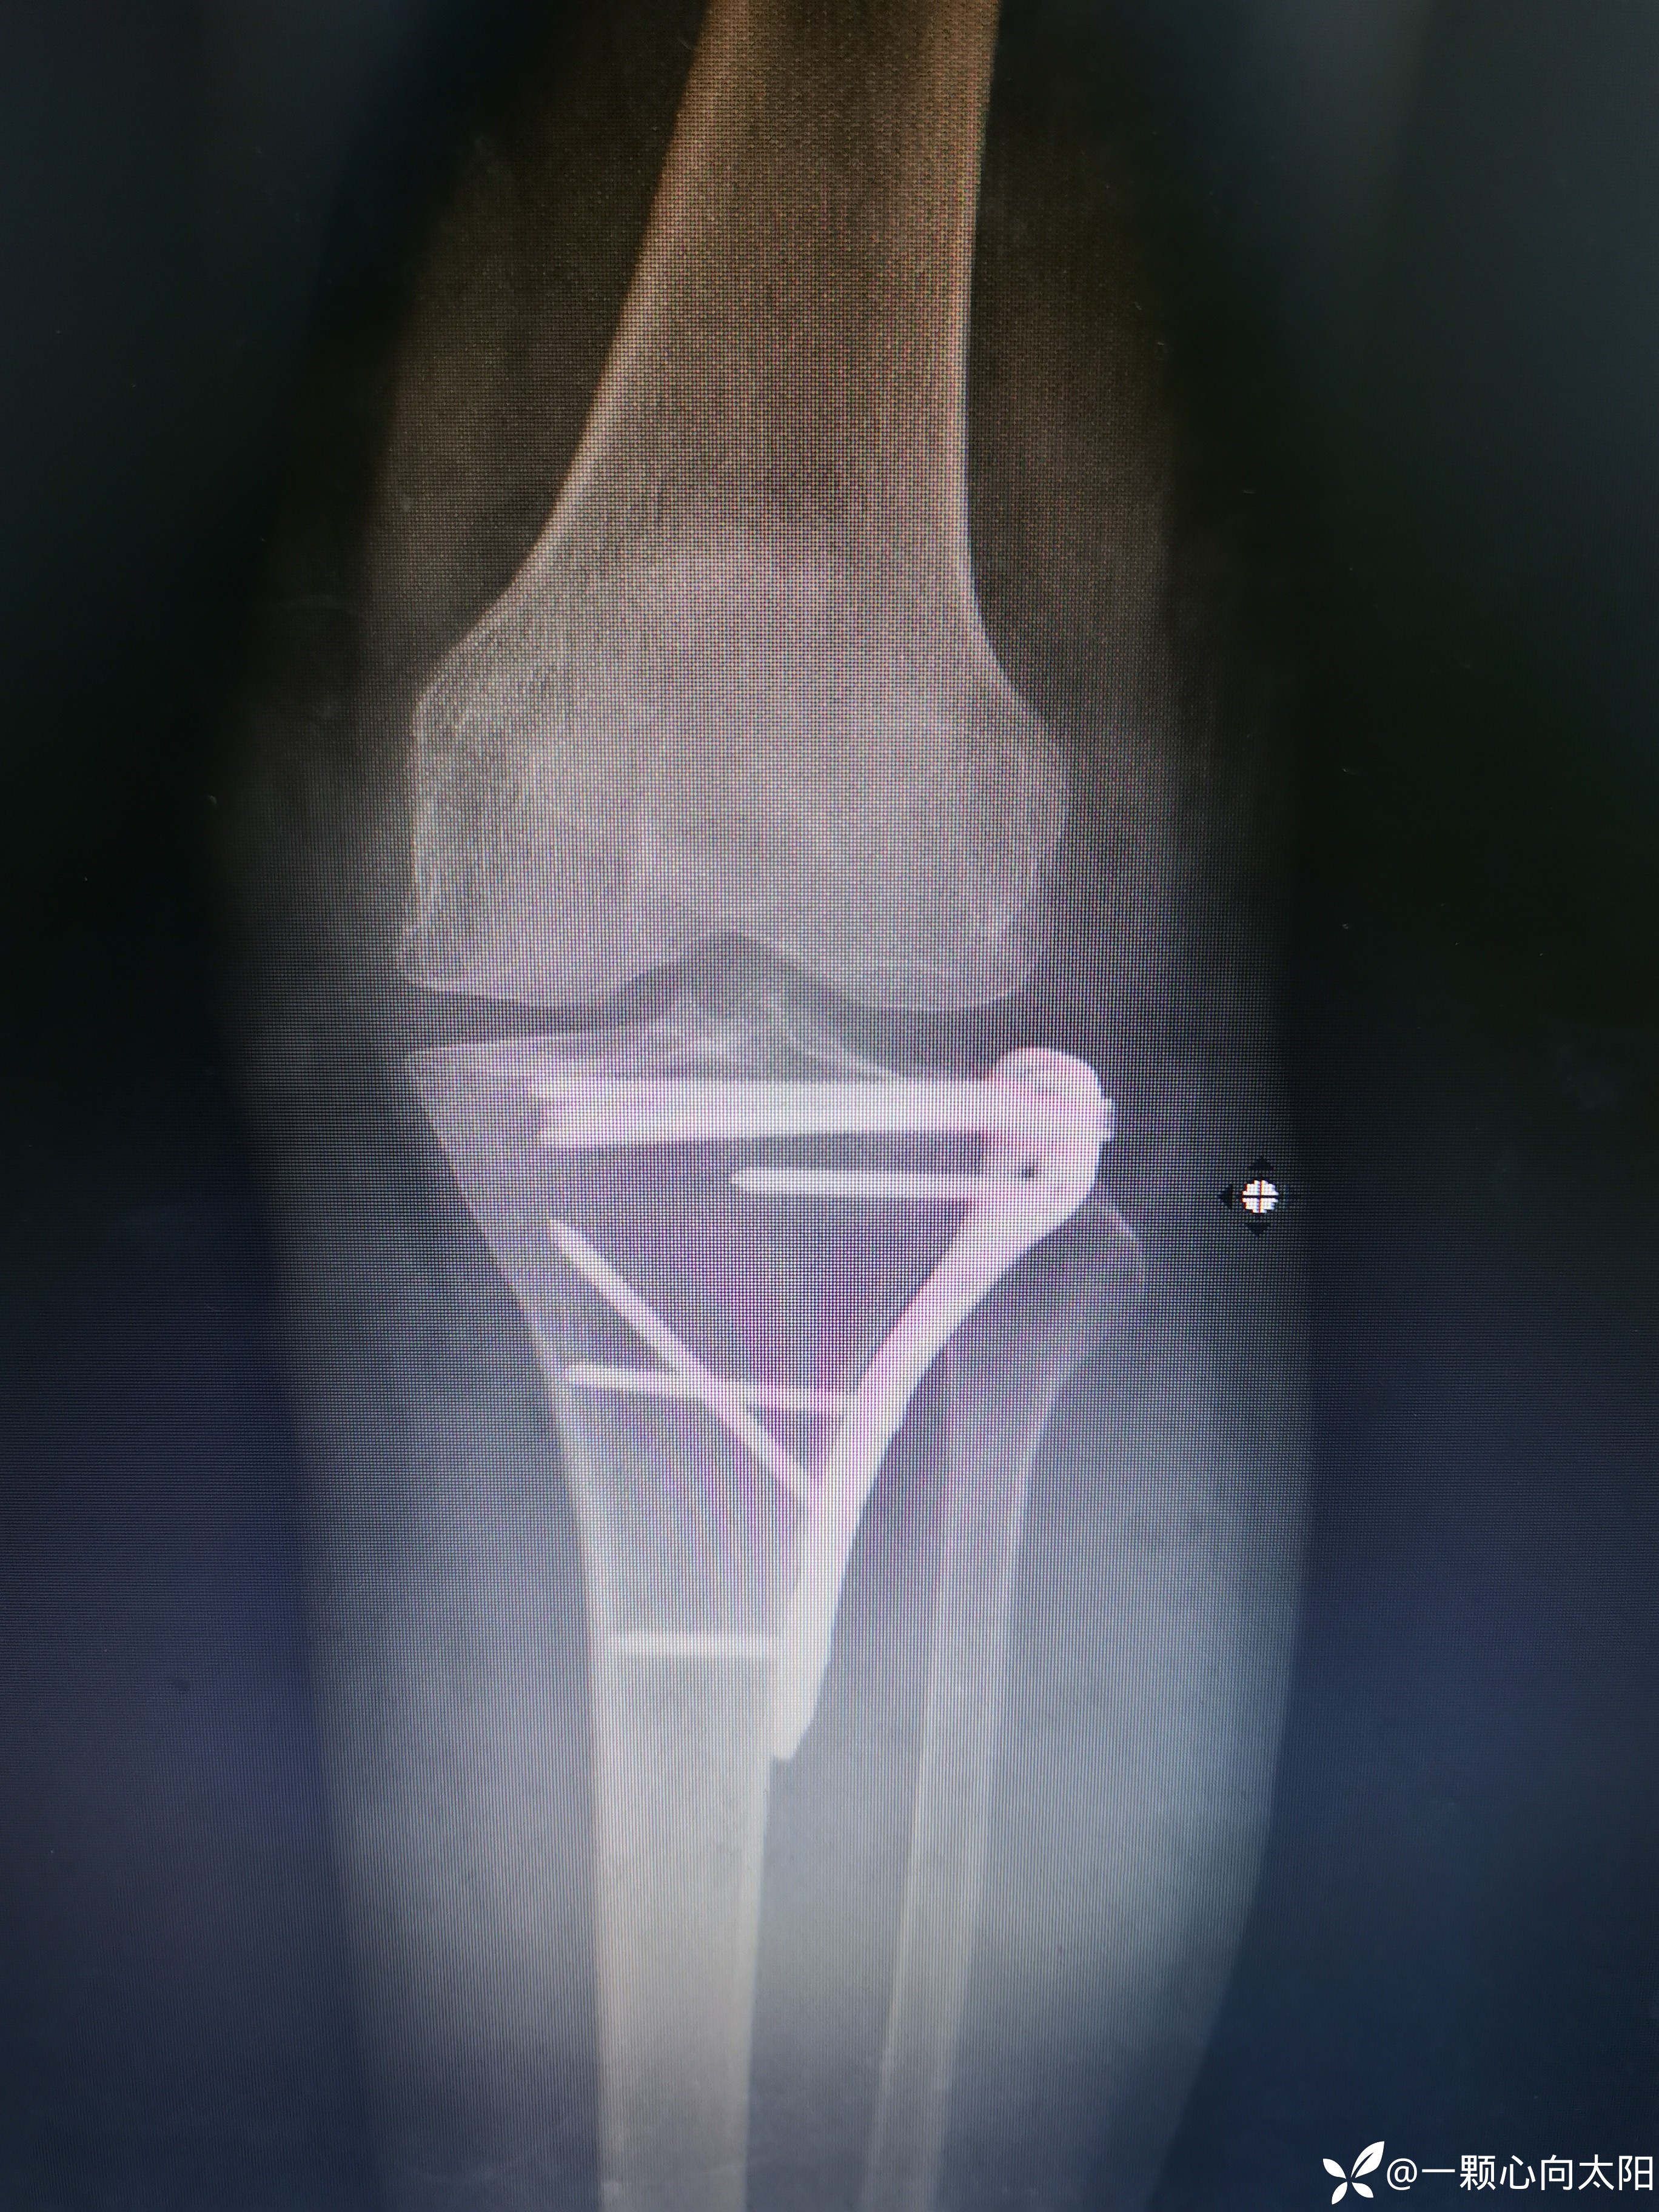

69岁,女性患者,以“外伤致左膝关节疼痛伴活动受限3小时”为主诉入院。

完善术前检查排除手术禁忌后行切开复位内固定术